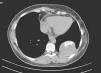

La TC torácica (fig. 1) mostró una masa de 6,5×5,7cm en contacto con la pared posterior con calcificación abigarrada en su interior y que tras la perfusión de contraste mostraba captaciones intensas focales dentro de la misma, sin otros hallazgos reseñables. Una PET demostró un depósito, con aumento periférico del metabolismo de 18FDG y área ametabólica en su interior, en el parénquima pulmonar izquierdo de unos 9cm de diámetro máximo y un índice de captación máximo de 4,4. Tanto el patrón metabólico, como los antecedentes planteaban como primera opción diagnóstica un quiste hidatídico, quedando en un segundo lugar la probabilidad de una neoplasia.